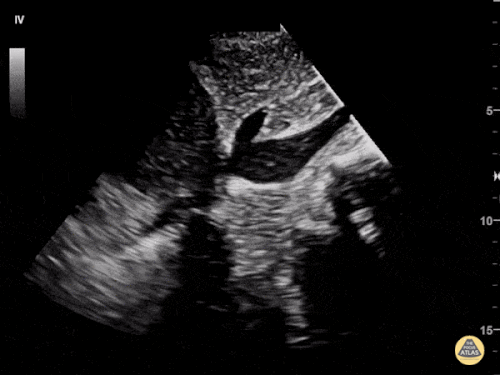

Apikal dört boşluk

Sağ ventrikül fonksiyonunun değerlendirilmesi

Sağ ventrikül, önceki bölümde anlatılan temel kardiyak pencereler kullanılarak değerlendirilebilir. Normalde sağ ventrikül düşük basınçlı bir odacıktır ve sol ventriküle kıyasla daha küçük görünür.

Sağ ventrikül disfonksiyonunda özellikle şu bulgulara bakılır:

Sağ ventrikül dilatasyonu

Septal bombeleşme (septal bowing)

Apikal dört boşluk görüntüsünde sağ ventrikül normalde sol ventrikülün yaklaşık üçte ikisi büyüklüğünde olmalıdır. Eğer iki ventrikül aynı boyutta görünüyorsa bu durum anormal kabul edilir ve dilatasyon düşündürür.

Bir diğer önemli bulgu McConnell belirtisidir. Bu bulgu, sağ ventrikül serbest duvarında hipokinezi bulunurken apeksin korunmuş olması şeklinde tanımlanır.

Apikal dört boşluk görüntüsü alınırken dikkatli olunmalıdır. Eğer görüntü aks dışı alınırsa sağ ventrikül kısalmış (foreshortened) görünebilir ve dilatasyon gözden kaçabilir. Bu hatadan kaçınmak için probu hafifçe döndürerek sağ kalbin en geniş göründüğü düzlemi yakalamak gerekir.